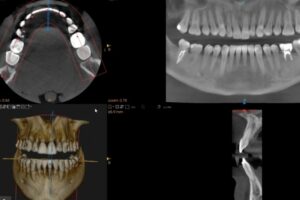

Mediante fotografías, vídeos y escaneos 3D obtenemos una visión integral de la estructura dental, el contorno gingival y la relación con los rasgos faciales.

2️⃣ Digitalización y simulación 3D

Con los datos obtenidos, realizamos un modelo digital exacto de tu boca y tu sonrisa.

Gracias al software de diseño, podemos simular diferentes versiones de tu sonrisa ideal y mostrarte cómo se vería antes de realizar ningún tratamiento.